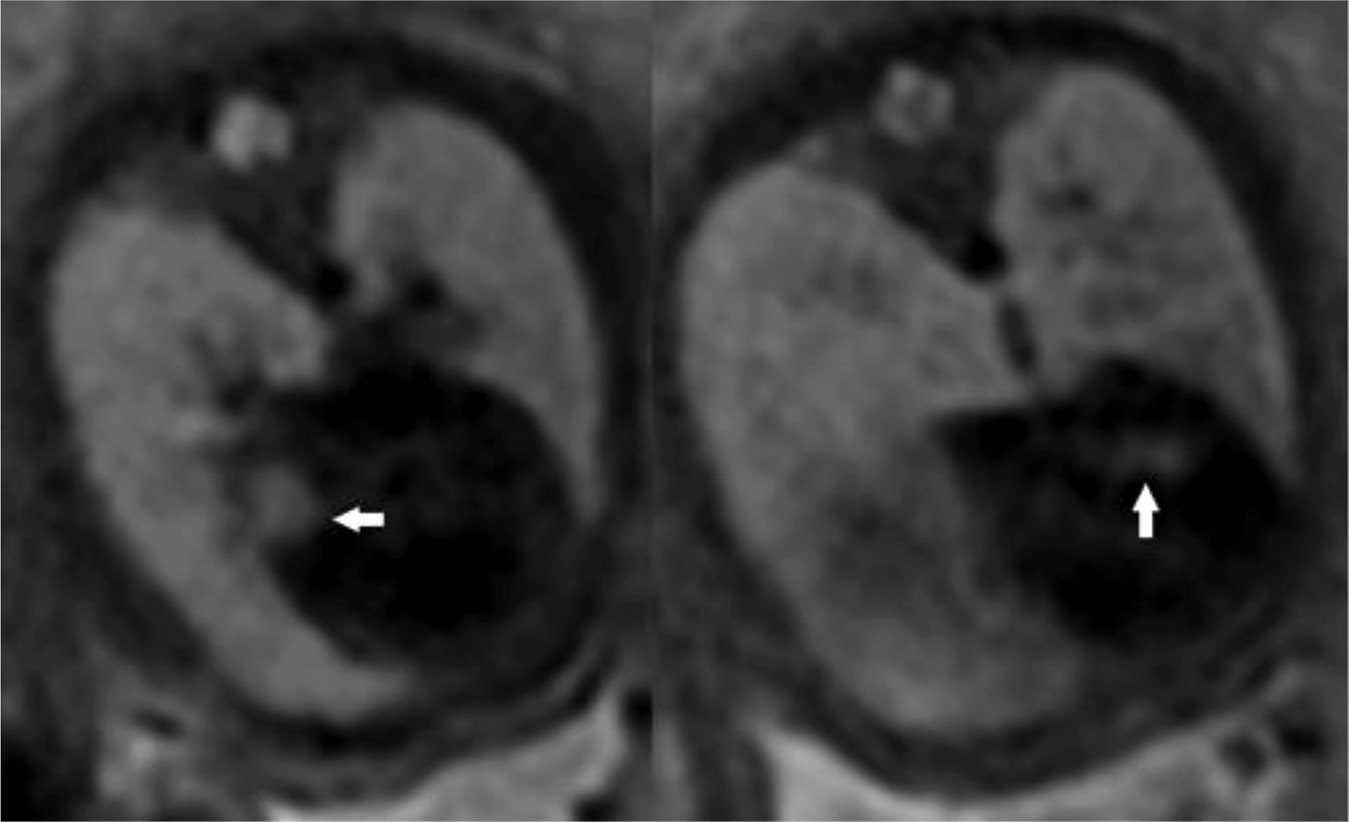

Через 2 месяца после рождения (16.11.2022) ребёнку грудного возраста проведена МРТ головного мозга. В белом веществе больших полушарий (лобные, теменные, височные и затылочные доли), преимущественно интра- и субкортикально, а также в паравентрикулярных отделах выявлены множественные участки патологического магнитно-резонансного сигнала с нечёткими и неровными контурами, имеющими тенденцию к слиянию:

- гиперинтенсивный — на Т2-ВИ;

- изогипоинтенсивный — на изображениях, полученных при последовательности инверсия–восстановление (FLAIR);

- гиперинтенсивный — на Т1-ВИ.

Мозолистое тело гипоплазировано. Таким образом, постнатальные изменения на изображениях МРТ совпадали с данными пренатальной диагностики в отношении наличия субэпендимальных узлов, которые являются патогномоничным признаком туберозного склероза. На Т2-ВИ субэпендимальные узлы имеют низкий сигнал, что соответствует процессам кальцинации в их структуре (рис. 4).

Рис. 4. Результаты магнитно-резонансной томографии головного мозга пациента в возрасте двух месяцев: a — изображения, полученные при использовании последовательности инверсия–восстановление с длинным T1 (FLAIR). В перивентрикулярных и субкортикальных областях выявлены множественные патологические очаги (белые стрелки); b — Т2-взвешенные изображения. Отмечен низкий сигнал от субэпендимальных узлов (чёрные стрелки), что свидетельствует об их кальцинации.